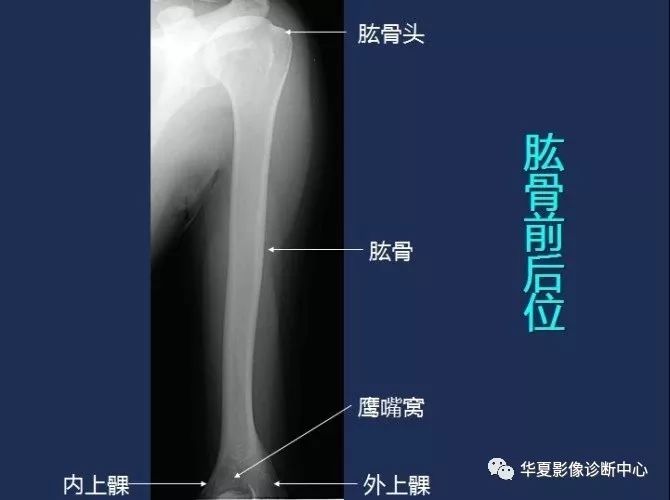

肱骨前后位

X线解剖图谱(肱骨)